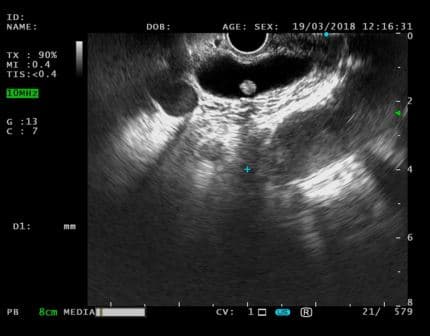

ЭУС-картина главного панкреатического протока